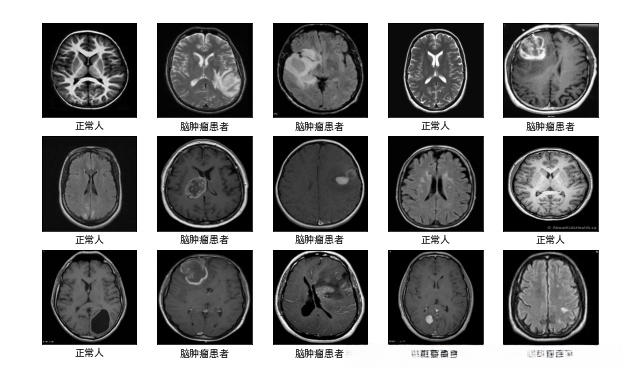

plt.figure(figsize=(10, 8)) # 图形的宽为10高为5

plt.suptitle("公众号(K同学啊)回复:DL+35,获取数据")

class_names = ["脑肿瘤患者","正常人"]

for images, labels in train_ds.take(1):

for i in range(15):

plt.subplot(4, 5, i + 1)

plt.xticks([])

plt.yticks([])

plt.grid(False)

# 显示图片

plt.imshow(images[i])

# 显示标签

plt.xlabel(class_names[labels[i]-1])

plt.show()